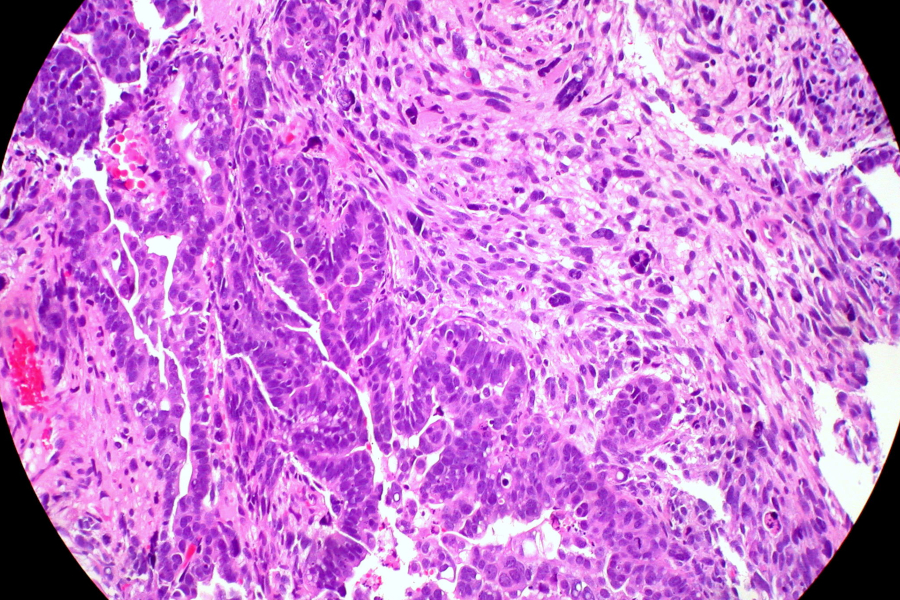

Inhibir la proteïna receptora (CXCR6) d'una molècula anomenada CXCL16 mitjançant fàrmacs o amb edició genètica podria frenar la metàstasi en pacients amb càncer d'endometri, a l'úter. Així ho suggereixen els resultats d'un estudi liderat per personal de l'Institut de Recerca Biomèdica de Lleida (IRBLleida) i la Universitat de Lleida (UdL) que s'acaba de publicar a la revista Cell Death & Disease, del grup Nature. Aquesta citocina forma part de les substàncies que les cèl·lules canceroses alliberen al seu entorn (secretoma) facilitant el creixement del tumor, la seua capacitat d'invasió i una major resistència als tractaments. La descripció d'aquest mecanisme molecular pot contribuir al desenvolupament de teràpies més eficaces.

L'equip ha treballat amb models de ratolí i mostres de teixit humà per identificar aquest mecanisme molecular a les cèl·lules afectades per la pèrdua d'un gen anomenat ARID1A. Així han comprovat que la inhibició de la proteïna CXCR6 o del seu receptor interromp les interaccions patogèniques, dificultant la migració de les cèl·lules canceroses i reduint la càrrega metastàtica. "Això suggereix una possible nova estratègia terapèutica per a pacients amb formes més agressives o avançades de la malaltia", ha explicat la primera autora de l'article, Cristina Megino Luque, que va llegir la seua tesi doctoral a la UdL i actualment treballa al Tisch Cancer Institute de Nova York.